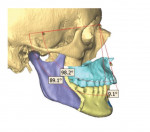

In the case presented, a 59-year-old male patient had severe OSA (AHI 45), decreased posterior airway space, and concomitant maxillofacial skeletal deformities (Angle class II malocclusion, maxillary and mandibular retrognathia, transverse maxillary hypoplasia, and transverse mandibular hypoplasia) (Figure 1 through Figure 4). Orthognathic surgical planning included tracings of a reconstructed lateral cephalogram to estimate postsurgical esthetic changes after advancements of 8 mm, 10 mm, and 12 mm (Figure 5). It is important to note that facial esthetics may change significantly, and this must be discussed in detail with the patient.

Virtual surgical planning in this case is demonstrated in Figure 6 through Figure 9: preoperative 3D CT imaging and planned surgical bony changes (Figure 6), preoperative 3D CT imaging and planned surgical soft-tissue changes (Figure 7), and examples of prefabricated cutting guides (Figure 8) and plates/screws for the maxilla (Figure 9). Careful attention must be paid to the root apices of the upper posterior and lower anterior teeth, the position of the inferior alveolar nerve and mental foramen, and any potential bony interferences after the reposition of the maxilla and mandible.